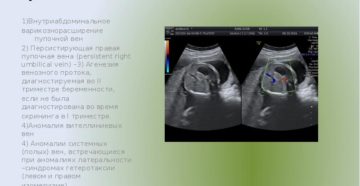

Персистирующая правая пупочная вена › Медикаменты 31.01.2020 РЦРЗ (Республиканский центр развития здравоохранения МЗ РК) Версия:…